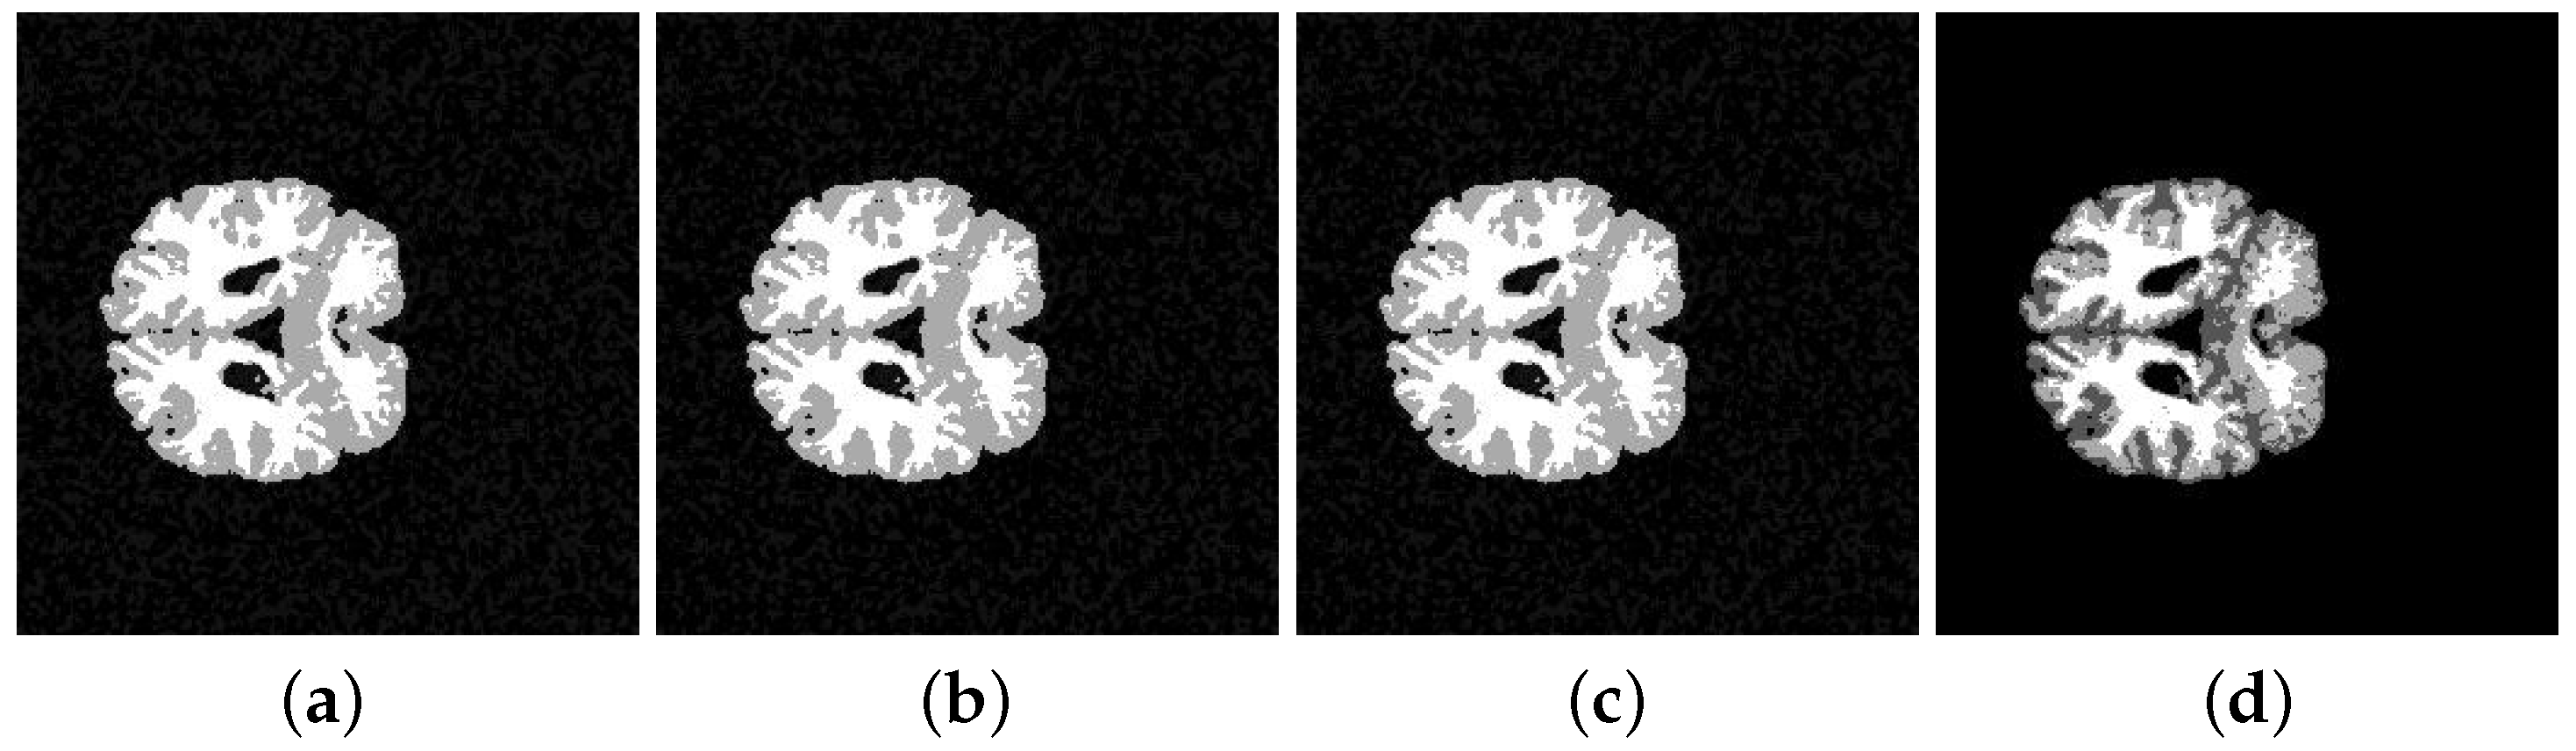

| Segmented Image | K-means | FCM | SFCM | KFCM |

|---|---|---|---|---|

| 202-3 original | 0.5842 | 0.5850 | 0.5832 | 0.5889 |

| 202-3 with noise | 0.5859 | 0.5873 | 0.5856 | 0.5845 |

| 205-3 original | 0.5793 | 0.5781 | 0.5758 | 0.5761 |

| 205-3 with noise | 0.5763 | 0.5787 | 0.5761 | 0.5782 |